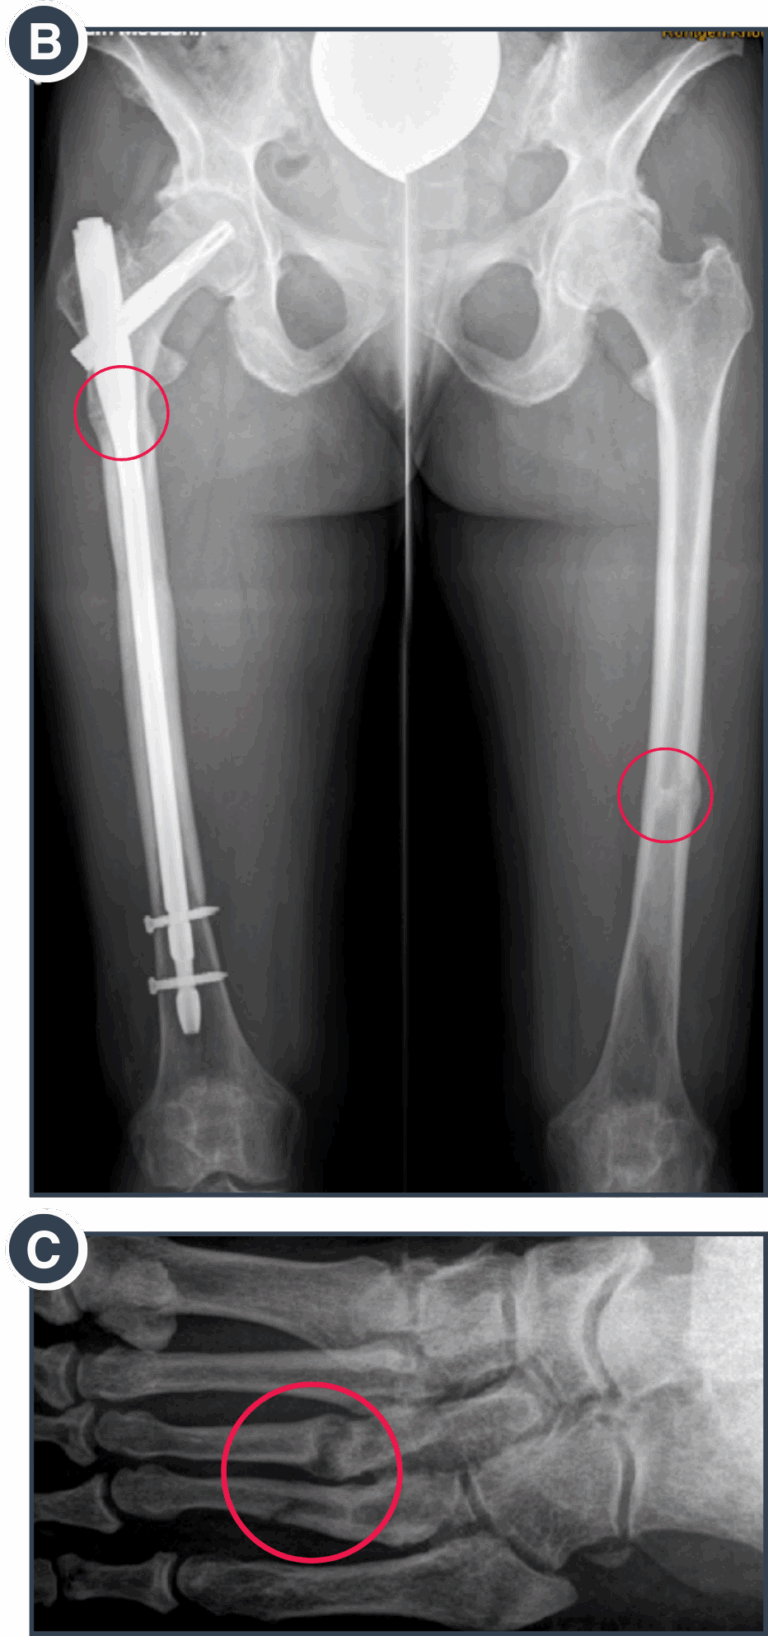

B: Course of fracture healing at 6 months after intramedullary rodding on the more critical right side and initiation of enzyme replacement therapy.

C: Metatarsal fractures due to increased mechanical strain over several weeks in association with enhanced everyday activities.